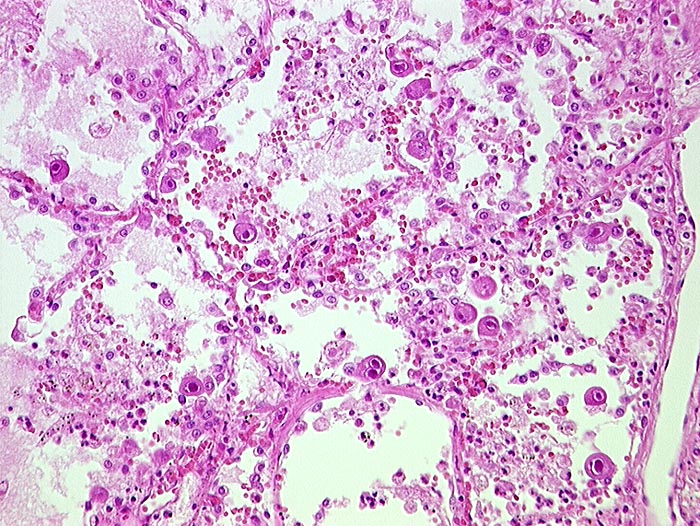

CMV (Zytomegalie) Pneumonie

Virale Kerneinschlüsse mit Halo in Pneumozyten (sogenannte Eulenaugenzellen)

HIV positiv seit 5 Jahren. Nachweis von zytomegalen Zellen im Hirn, in der Lunge, im Gastrointestinaltrakt, den Nieren und der Nebenniere. Zusätzlich bakterielle Pneumonie.